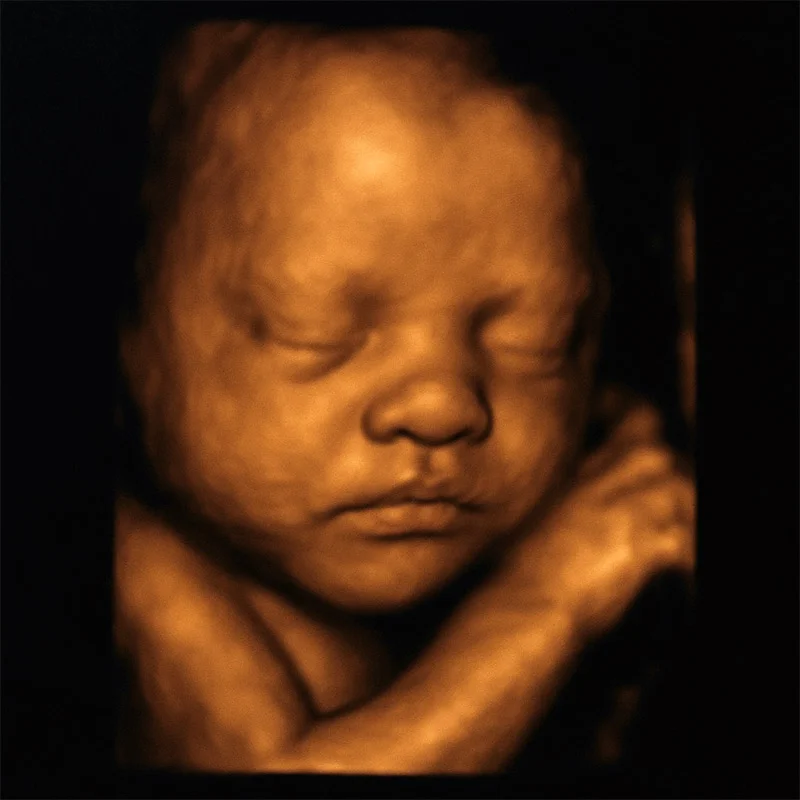

USG 4D to zaawansowana technologia ultrasonograficzna, która pozwala na uzyskanie trójwymiarowego obrazu płodu w czasie rzeczywistym – czyli w formie filmu wideo.

W odróżnieniu od tradycyjnego USG 2D, które pokazuje jedynie przekrój anatomiczny w dwóch wymiarach, USG 4D oferuje dynamiczny, realistyczny podgląd dziecka w łonie matki.

Można zobaczyć, jak dziecko się porusza, dotyka twarzy, a nawet ssie kciuk.

To badanie jest nie tylko źródłem wzruszeń, ale przede wszystkim narzędziem wspierającym lekarza w diagnostyce ewentualnych wad rozwojowych twarzy, kończyn czy narządów wewnętrznych.

Obrazowanie przeprowadzono przy użyciu aparatu USG z funkcją 3D/4D. Dzięki dobrej widoczności i prawidłowej pozycji płodu uzyskano wysokiej jakości obrazy.

- wyraźne zarysy twarzy i mimikę dziecka

- spontaniczne ruchy rączek i nóżek

- ssanie kciuka

Obraz 4D umożliwił szczegółową ocenę struktur twarzy oraz kończyn, co zwiększyło precyzję diagnostyczną badania.